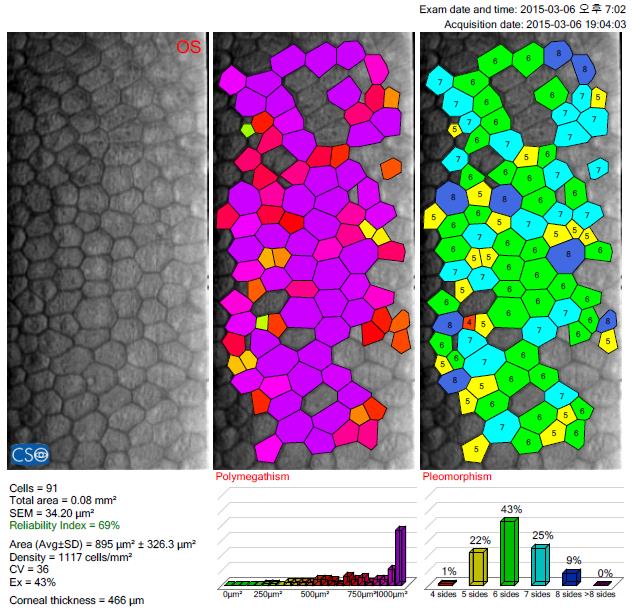

이분의 경우, 렌즈 한쪽이 고정이 안되면서 눈을 깜빡일 때마다 눈을 자극했고, 그 결과 내피세포가 상당히 손상이 되었습니다. 당시 병원에 오셨을 때 내피세포는 1000개 초반이었습니다. 방치됐더라면 눈에 어떤 문제가 진행되고 있는지, 알지 못하고 계셨을지도 모릅니다. 부작용은 수술 자체가 아니라 수술 후 관리를 소홀히 했을 때 발생한다는 사실을 다시 한번 깨닫게 했던 사례였습니다.

▼내원 당시 내피세포 검사 결과